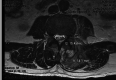

A 54-year-old man with a past medical history significant for sciatica, as well as multiple orthopedic surgeries with hardware, was transferred from an outside rural facility for further workup of a two-month history of progressive back pain and muscle weakness. Investigations ultimately revealed abnormal enhancement from T11 to sacrum, with a large epidural abscess from L5 to the sacrum, best visualized on an MRI. Following the MRI confirmation of loculated complex thoracolumbar abscess, neurosurgery performed a left L3-S1 unilateral laminotomy and evacuation of compressive multiloculated epidural abscesses. The patient was then treated with empirical antimicrobial coverage for epidural abscess with vancomycin and ceftriaxone, which was narrowed to cefazolin based on positive methicillin-susceptible Staphylococcus aureus (MSSA) wound cultures obtained in the operating room. The patient completed a total six-week course of antibiotic therapy. Apart from some superficial wound dehiscence postoperative, the patient ultimately recovered well and had a resolution of most presenting symptoms.